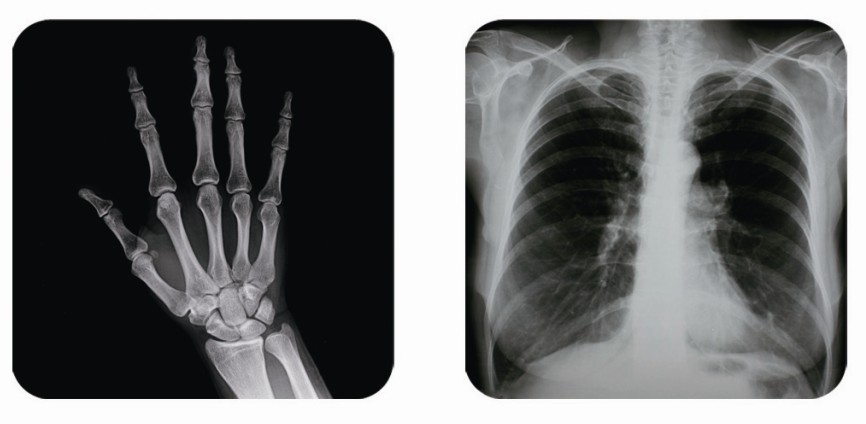

傳統胃腸造影檢查,病變顯示率低,輻射劑量大。普朗醫療器械公司生產的幾款多功能腸胃造影x光機,更能滿足不同等級不同規模的大小醫院選擇,從臨床及科研都很好。尤其最新的PLD8800多功能腸胃造影x光機用途更為廣泛。多功能腸胃造影x光機是目前各大醫院最普及的且用途最廣的一種X光機。普朗醫療的胃腸機功能多,簡便易用,能保證圖像質量,該機采用高制式電視系統,優秀的數字化系統能使多功能腸胃造影x光機的性能得到提高,應用范圍獲得極大的拓寬。

1、一般應用:數字透視,動態及多方位觀察器官病變,圖像更清晰,并可保留末幀圖像;既可使用暗盒完成常規X線拍片,這是其最大的優勢,拍片質量大大提高。